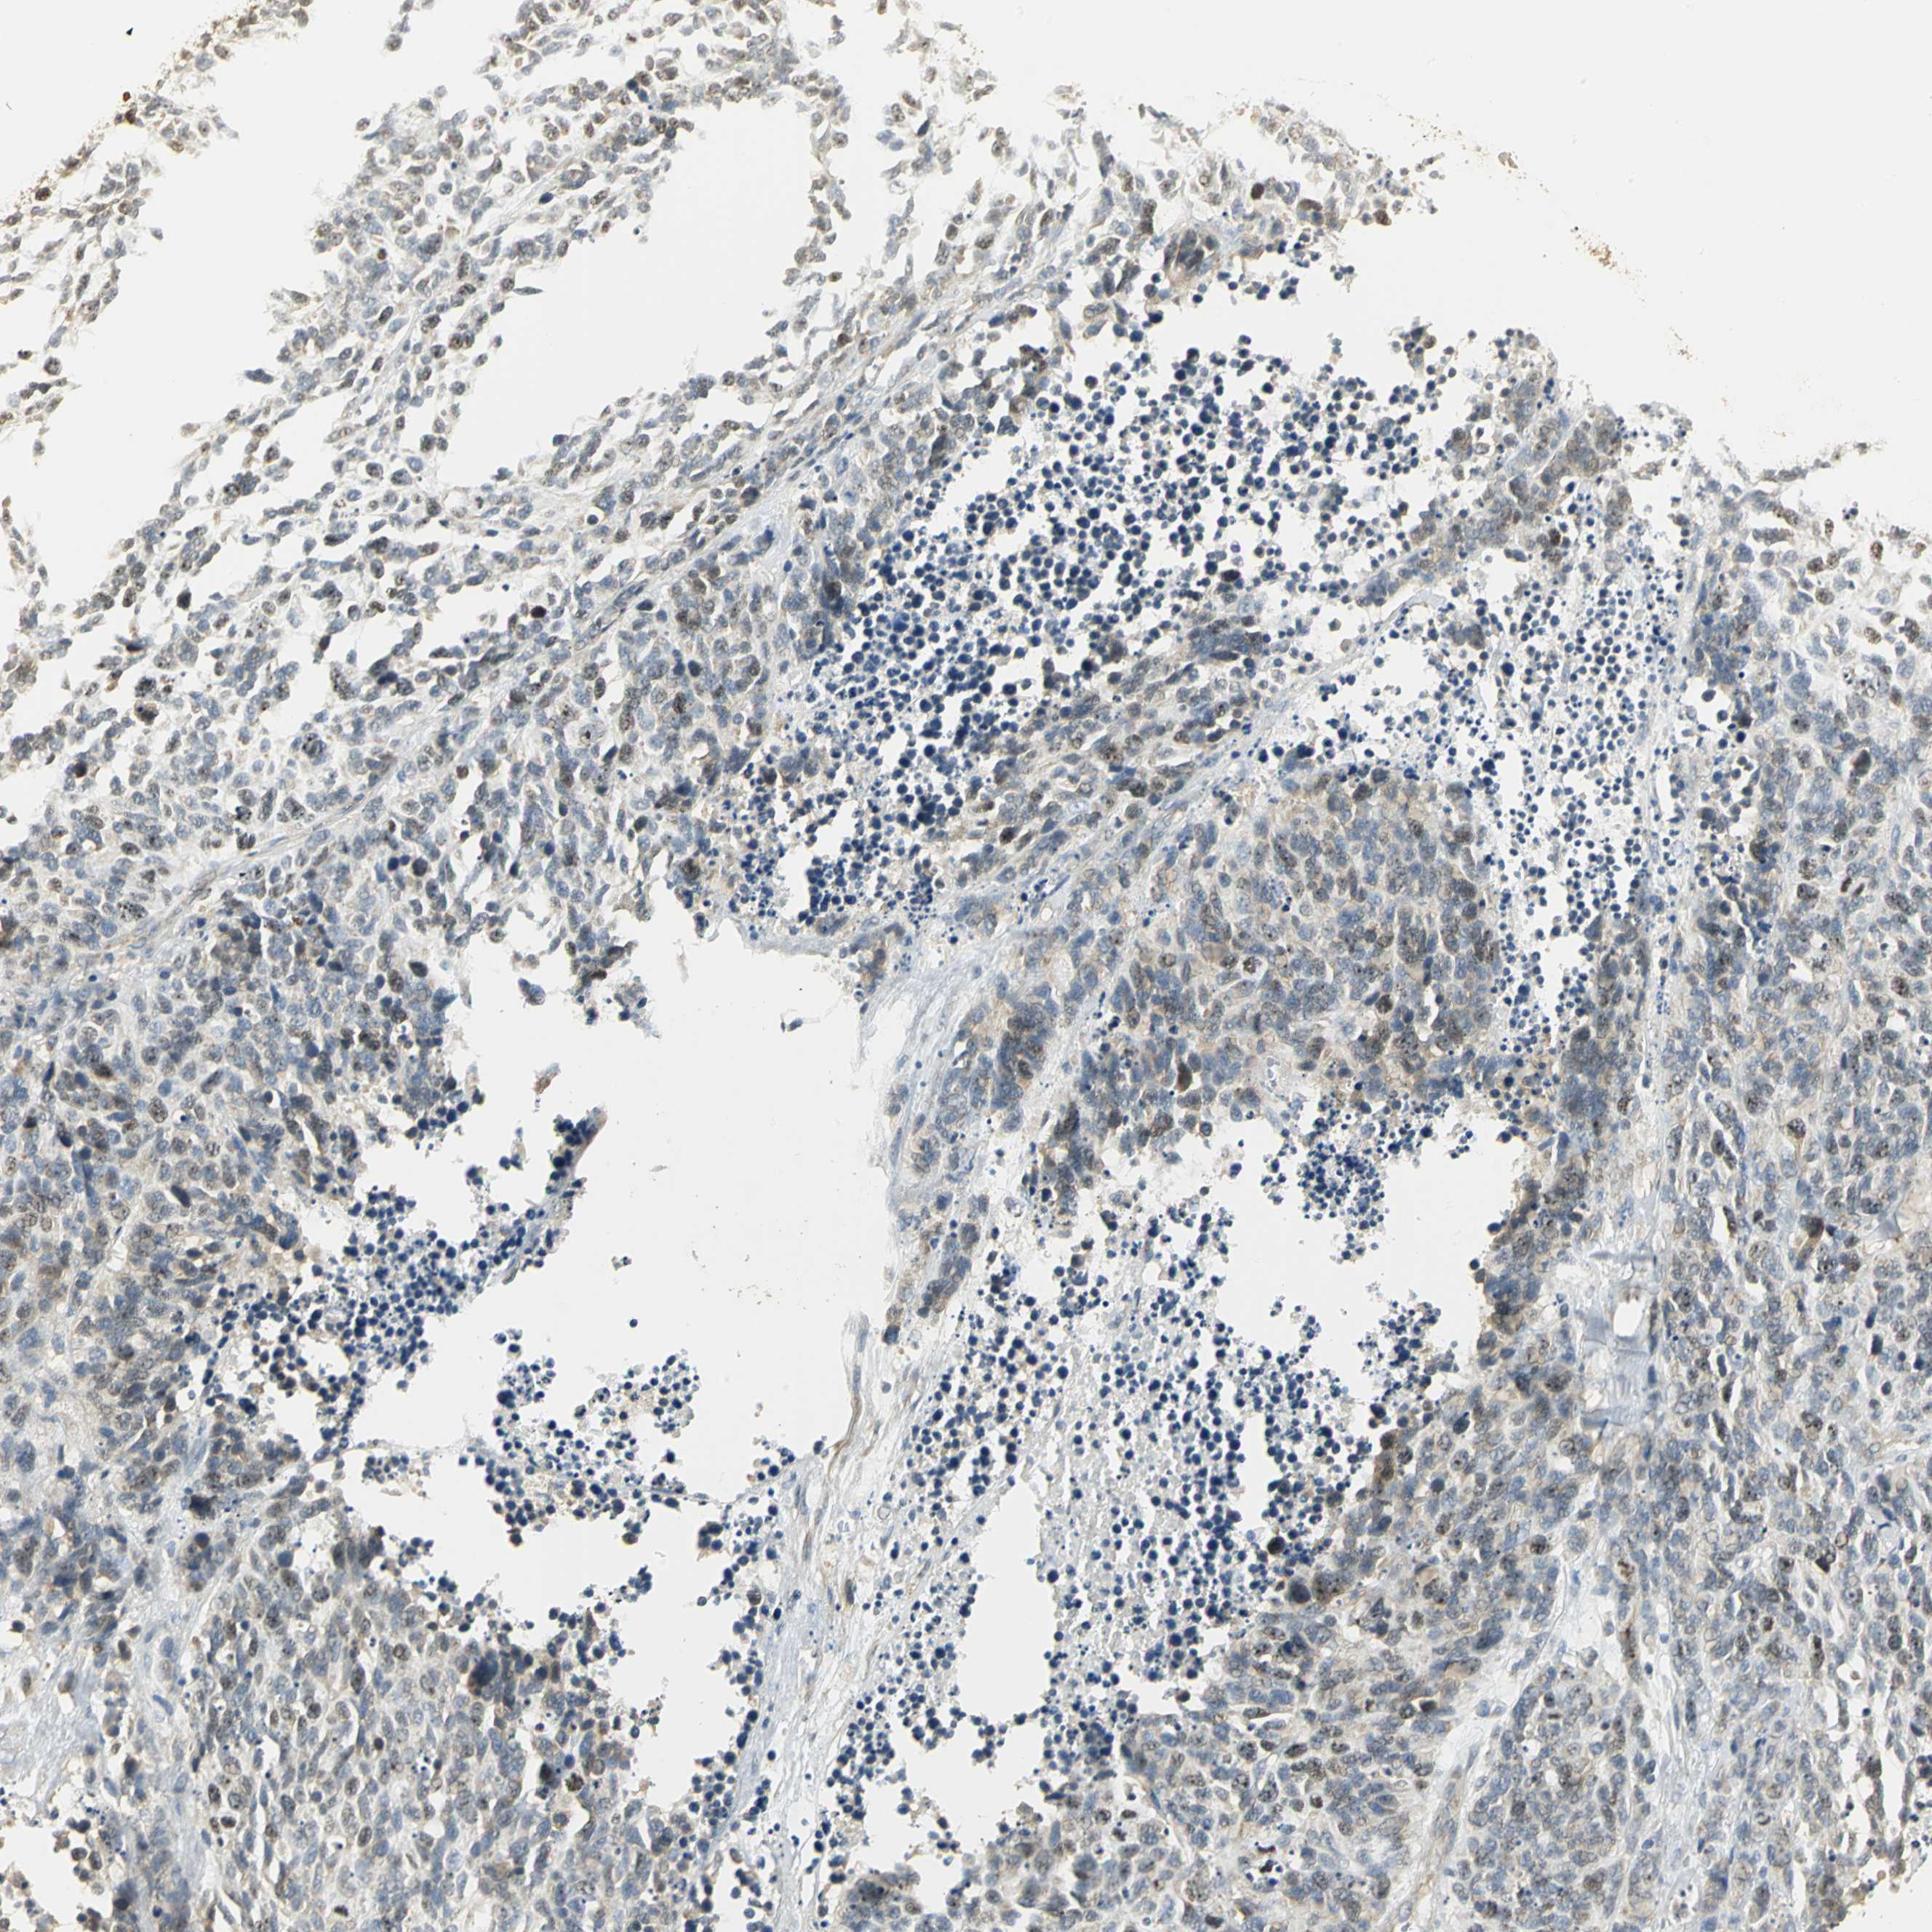

CANCER LUNG CANCER Show tissue menu

Lung cancer

Human cancer